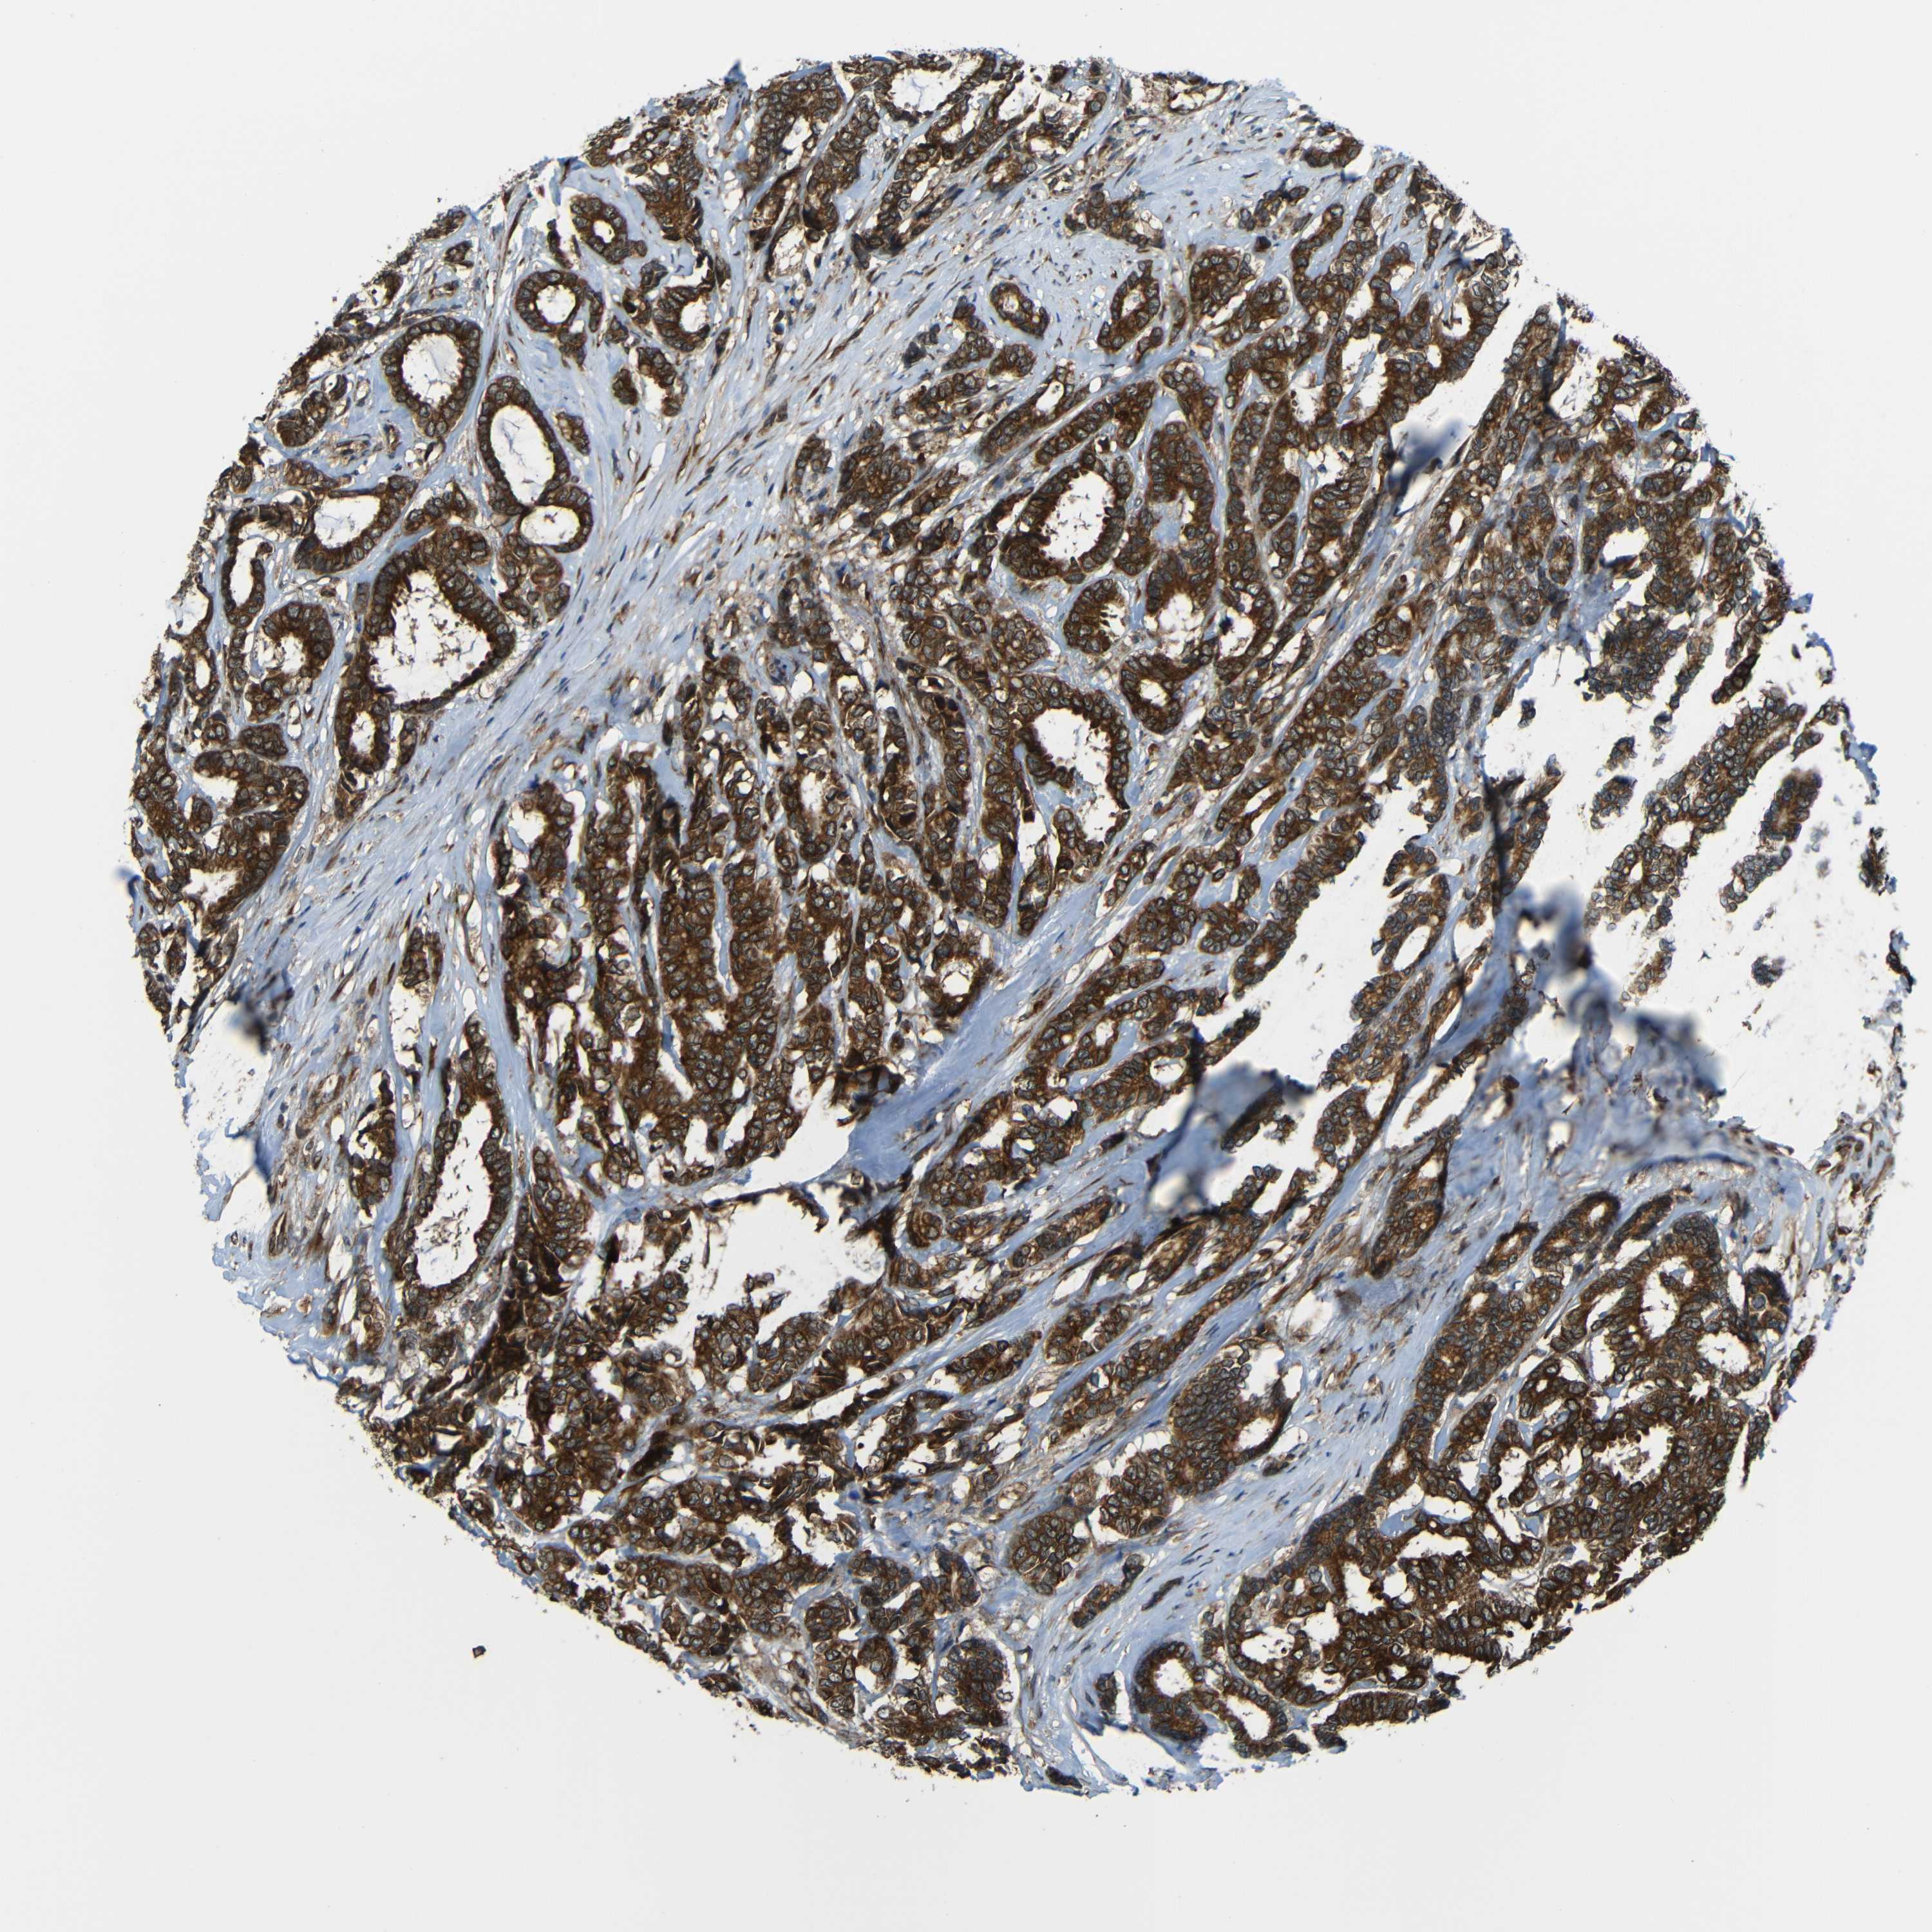

CANCER BREAST CANCER Show tissue menu

BRCA TCGA BRCA VALIDATION PROTEIN EXPRESSION